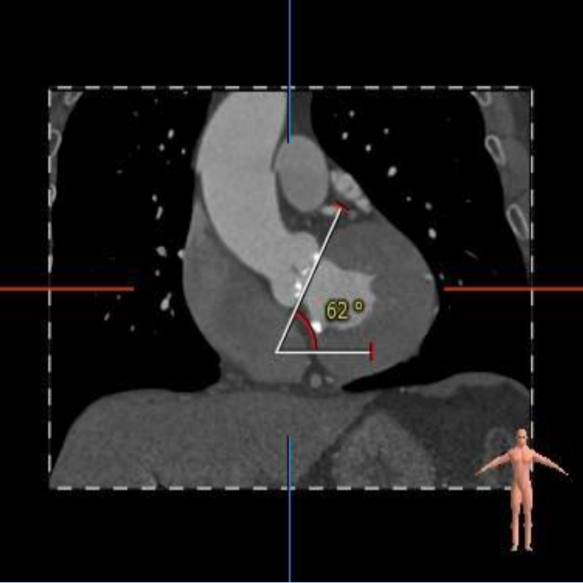

瓦氏窦内径、窦管交界内径、升主内径可,主动脉瓣环与水平面夹角62°,横位心,主动脉弓角弓距可。